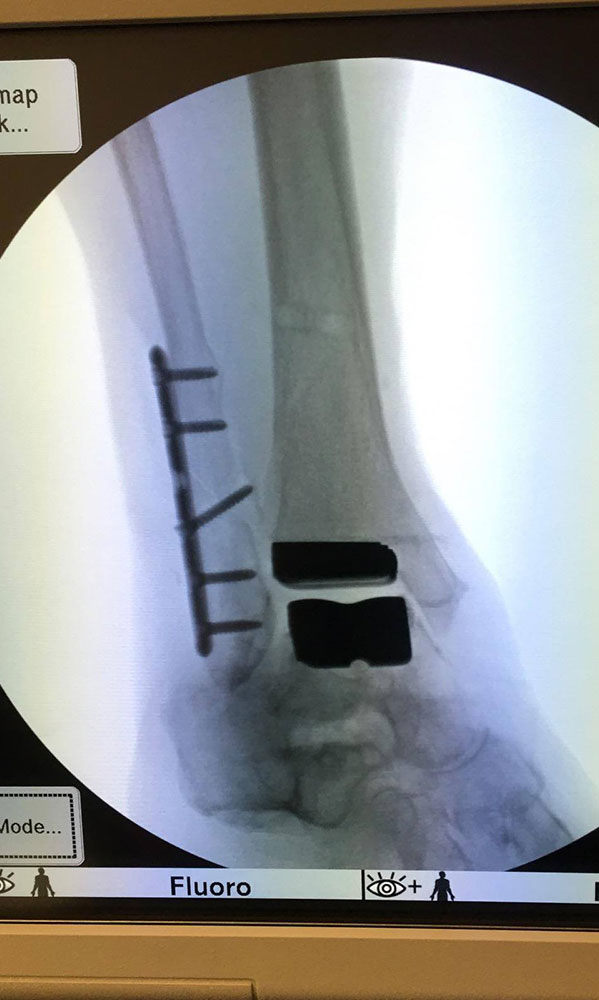

"Surgical misadventure" by another surgeon about 8 years ago. The wrong fixation was used for a flatfoot repair, & the deformity was not corrected. Patient came in with severe foot & ankle pain, with no arch at all. She was unable to play with her grandchild because the pain was so bad, & because she felt unsteady. The old hardware was removed, a lateral calcaneal lengthening osteotomy was performed along with a medial column/1st ray realignment. The ankle was painfully arthritic, & patient elected a total ankle replacement vs. an ankle fusion. She is now able to walk pain free & play with her grandchildren!